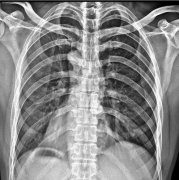

医用DR设备是如何减低辐射的

医疗DR设备旨在产生高质量的图像,同时减少产生图像所需的辐射剂量。利用数字技术,医疗DR设备可以通过较低的辐射水平获得内部结构的图像。这使得它成为医生和病人的 个很好的...更多 -

便携式移动DR是一款什么样的DR

便携式移动DR是 种全新的数字化直接成像系统,其拥有与传统X光成像相比更高水平的成像质量、更低辐射量、更快捷的检查速度以及更高的检查成功率等重要 势。同时,作为 款具...更多 -

移动DR的临床用途

移动数字放射照相(DR)是 种使用便携式设备捕获放射图像的现代技术。通过提高诊断成像的速度和质量,移动DR的临床应用改变了医疗行业。...更多 -